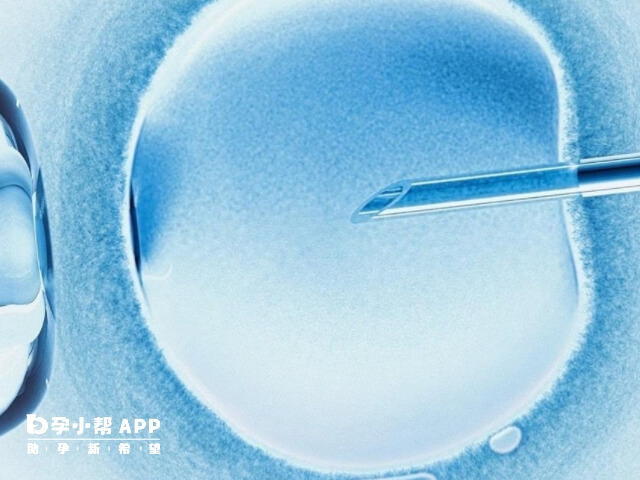

女人有梅毒可不可以做人工授精

如果女性曾经感染过梅毒,但经过规范的治疗之后,且梅毒血清检查或滴度持续稳定在低水平,那么这种情况下是可以做人工授精的。但如果女性处于梅毒感染活动期,此时具有传染性,那么就不可以做人工授精,否则可能会通过胎盘传染给胎儿,导致流产、早产等风险,不利于优生优育。

梅毒女人可以做人工授精的情况

人工授精过程中需严格无菌操作,避免精液或阴道分泌物传播病毒。若滴度未达标,可能导致胎儿先天性梅毒、流产或畸形。所以梅毒女人可以做人工授精前,需要满足以下条件。